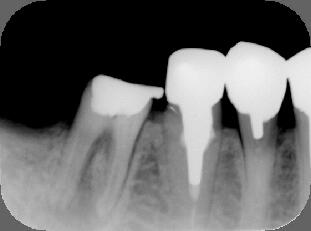

(1)不十分な根管(神経の通っていた管)治療が原因で右下の顎が腫れています。(↑病巣

当初は抜歯を考慮しました(上左図)が、根の治療を丁寧に行うことによって、半年後には

ほぼ問題の無い程度(上右図)にまで骨が修復され十分に機能が回復されました。